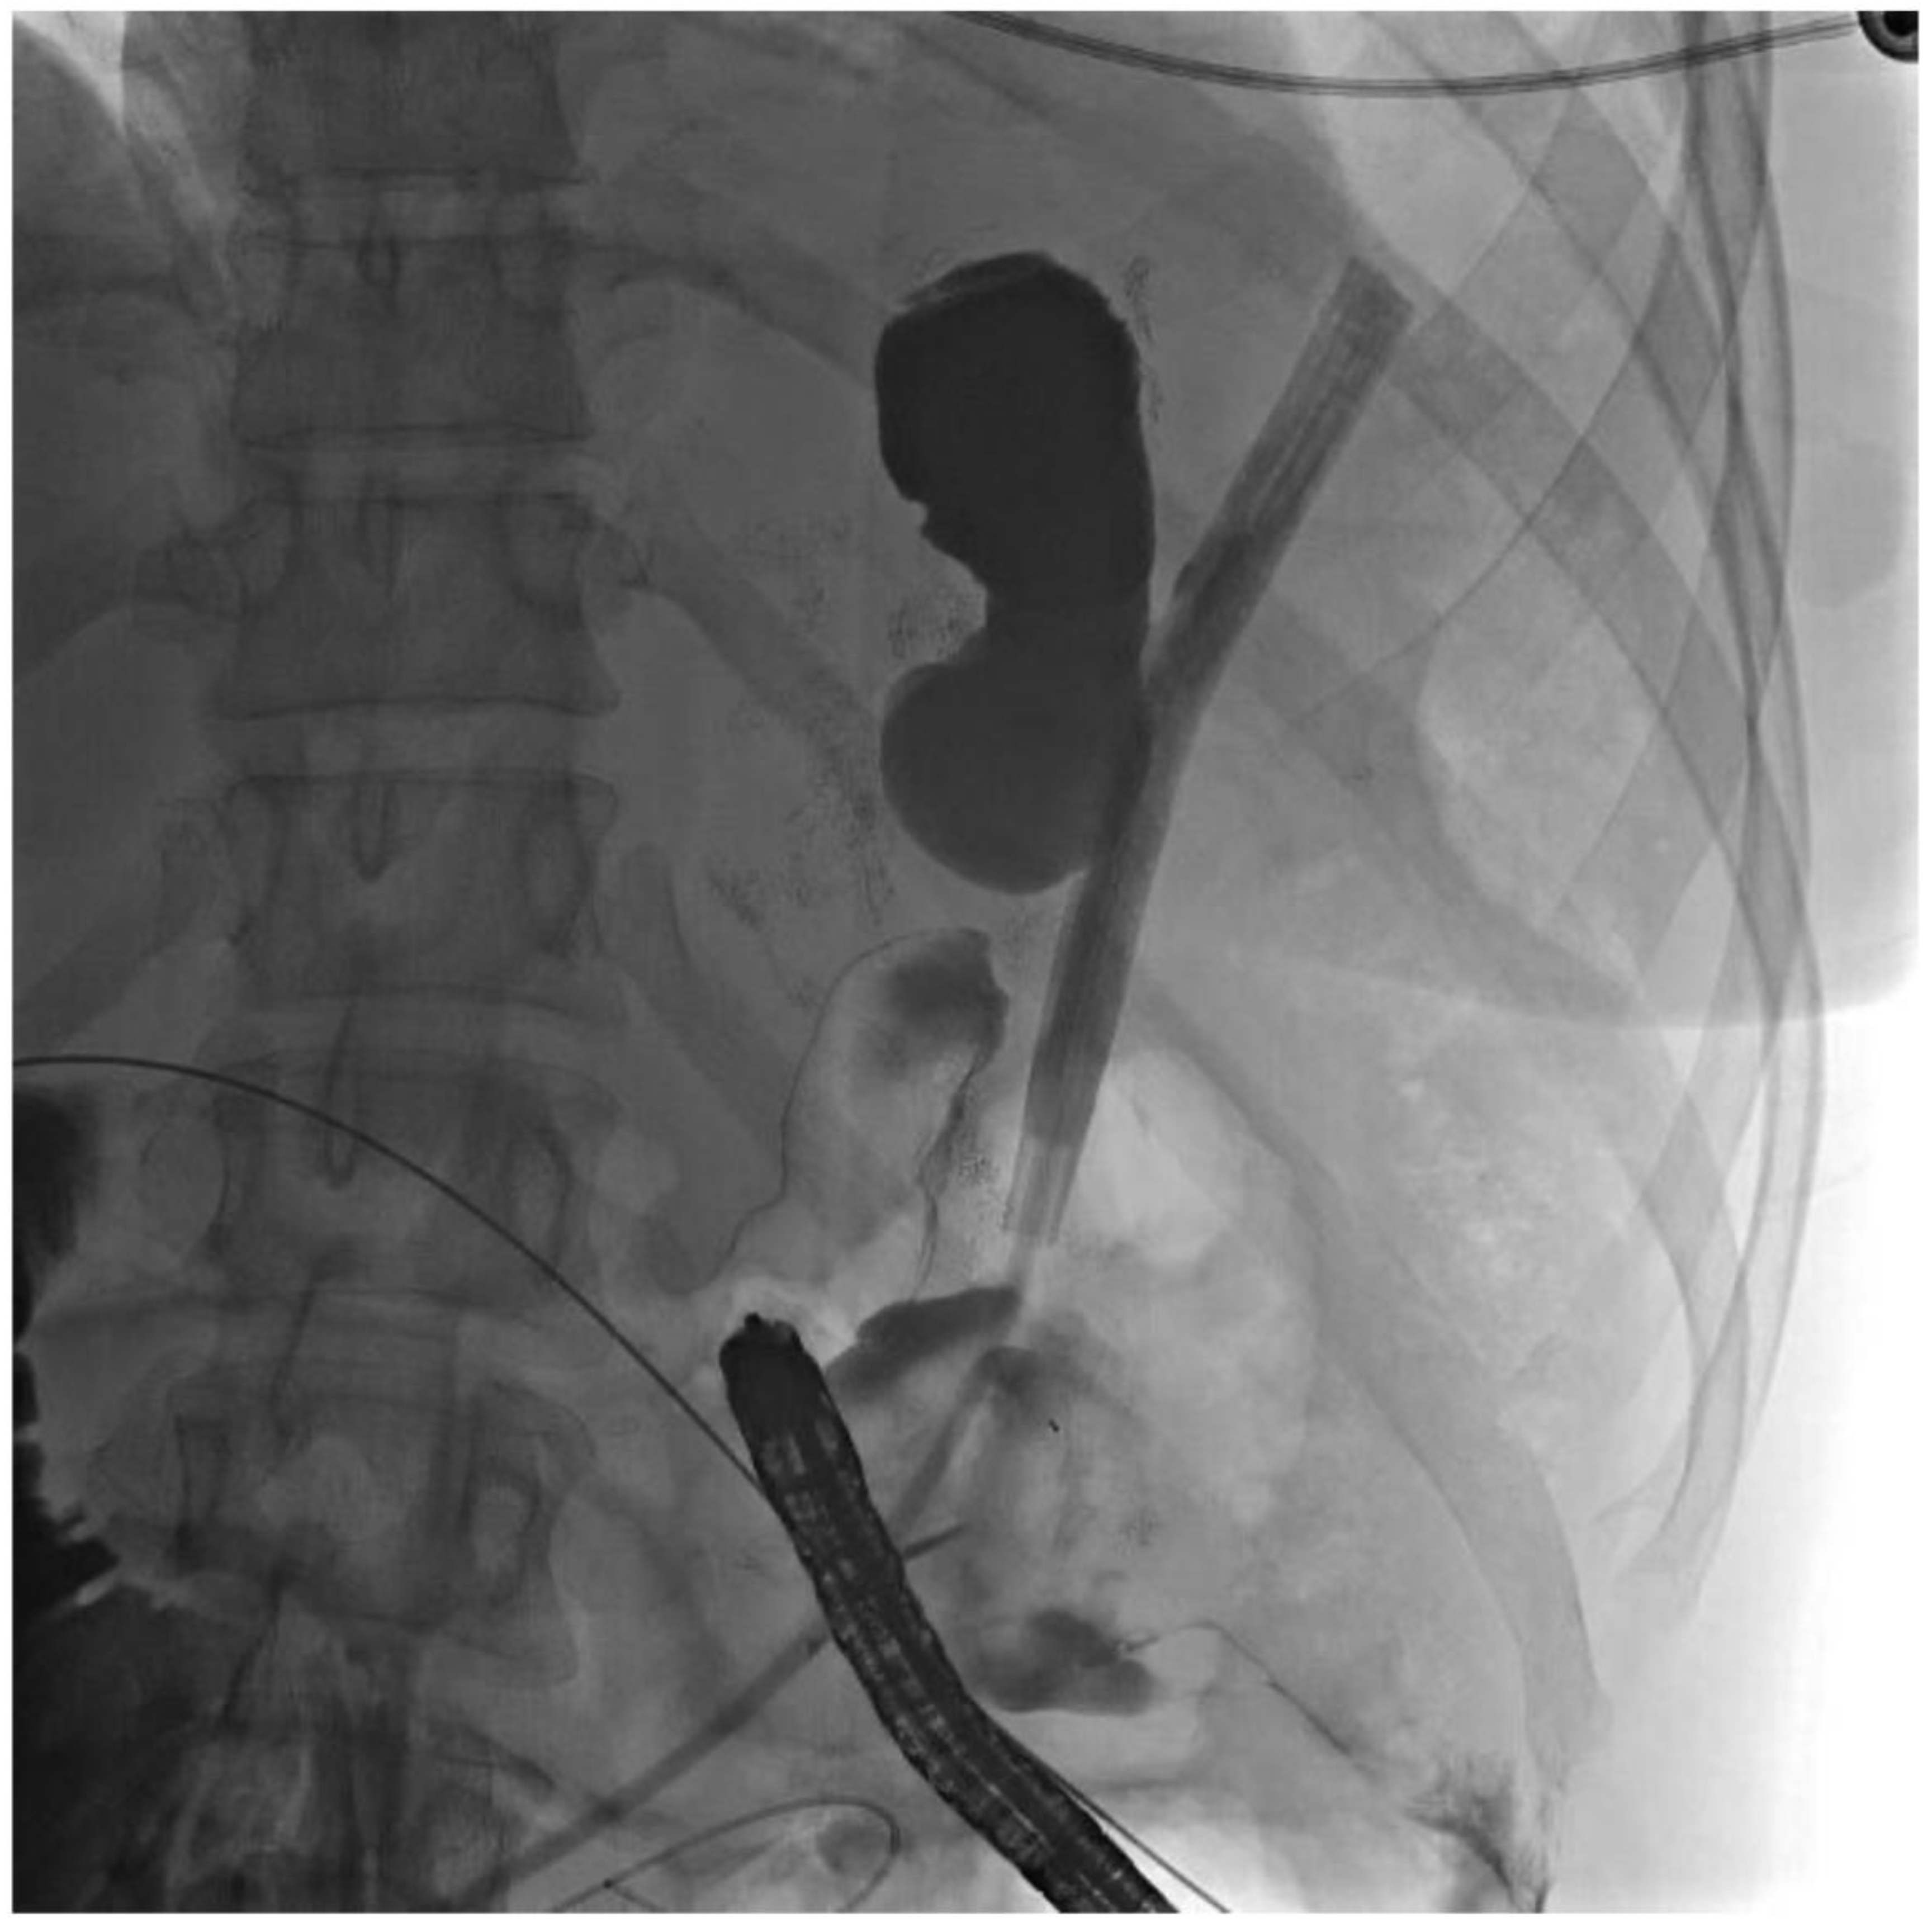

2. Detailed Case Description